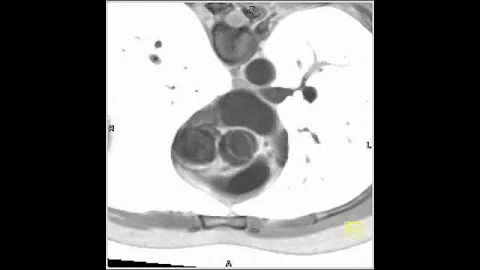

4-d Mri Of Bicuspid Aortic Valve Disease

Michael Markl, PhD, director of Cardiovascular Magnetic Resonance Imaging (MRI) Research Operations, is using 4D flow ...